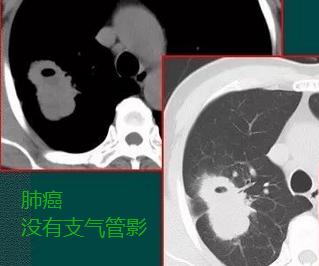

也许读者朋友对上面的文字内容不够理解,我们再看几张类似的肺癌的肿块图:

肿块边缘清晰,没有云雾状影,空洞呈偏心性,空洞壁没有支气管,病理证实为肺腺癌

抗炎治疗无效,病灶逐渐增大,肺癌